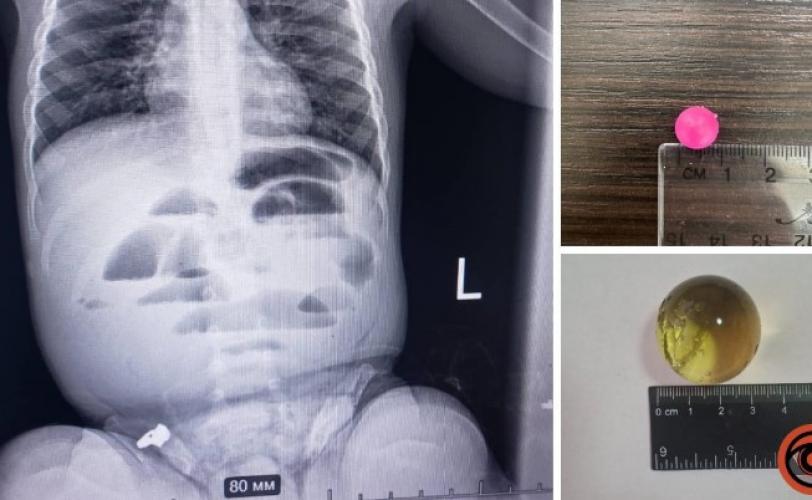

У Дніпрі дитина віком 1 рік і 8 місяців проковтнула гідрогелеву кульку. Її доставили до лікарні з підозрою на кишкову непрохідність. Медики зробили рентген і побачили, що кишківник заблокований. Під час операції виявили, що кулька всередині розрослася до трьох сантиметрів і перекрила шлях їжі.

Лікарі вчасно дістали кульку та наклали шви. Дитину перевели до реанімації. Медики нагадують батькам: такі кульки небезпечні, бо можуть рости всередині організму.